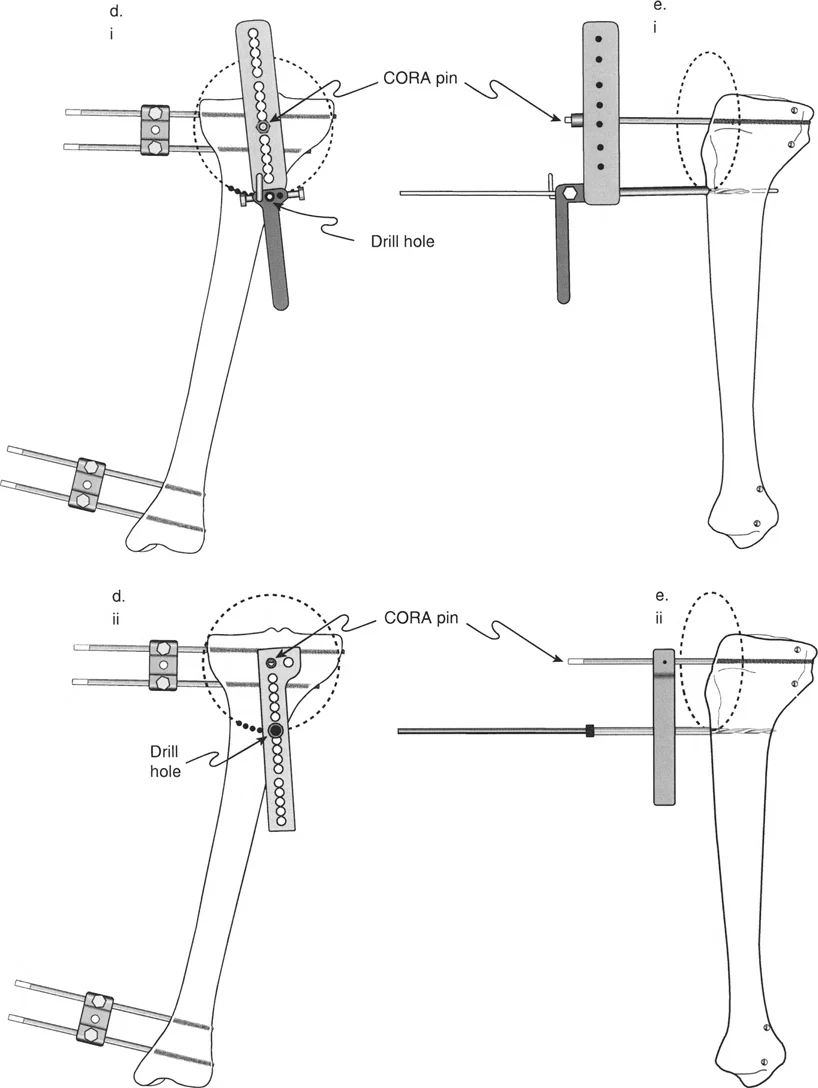

2. التدخل الجراحي: قطع العظم (Osteotomy)

العملية الجراحية الأكثر شيوعاً لتصحيح تشوه الانزياح هي "قطع العظم" (Osteotomy). تتضمن هذه العملية قطع العظم في مستوى التشوه أو بالقرب منه، ثم إعادة محاذاة أطراف العظم وتثبيتها في الوضع الصحيح.

- مبادئ تصحيح الانزياح:

- قطع عظم واحد مع تصحيح الانزياح المباشر: يتم قطع العظم في مستوى الانزياح، ثم يتم تحريك أطراف العظم مباشرة لإعادة المحاذاة وتثبيتها.

- قطع عظمين مع تصحيح زاوي معاكس: يمكن تصحيح الانزياح عن طريق إجراء عمليتي قطع عظم في مستويين مختلفين، مع تصحيح زاوي معاكس في كل مستوى. هذا النهج يسمح بإعادة المحاذاة دون إزاحة مباشرة لأطراف العظم في مستوى القطع.

خطوات العملية الجراحية (بشكل عام):

- التخطيط الدقيق: قبل الجراحة، يقوم الأستاذ الدكتور محمد هطيف بإجراء تخطيط جراحي مفصل باستخدام صور الأشعة السينية والتصوير المقطعي المحوسب. يتضمن ذلك تحديد الموقع الدقيق للقطع، مقدار التصحيح المطلوب، ونوع التثبيت الذي سيتم استخدامه.

- الوصول الجراحي: يتم عمل شق جراحي للوصول إلى العظم المتأثر.

- قطع العظم: يتم قطع العظم بدقة باستخدام أدوات جراحية متخصصة.

- إعادة المحاذاة: يتم تحريك أطراف العظم بعناية لإعادة محاذاتها في الوضع الصحيح، مع تصحيح الانزياح وأي انحرافات زاويّة مصاحبة.

- التثبيت: بعد إعادة المحاذاة، يتم تثبيت العظم باستخدام:

- المسامير والصفائح (Plates and Screws): وهي الطريقة الأكثر شيوعاً، حيث توفر تثبيتاً داخلياً قوياً.

- المسامير داخل النخاع (Intramedullary Nails): تستخدم في العظام الطويلة، حيث يتم إدخال مسمار معدني داخل قناة نخاع العظم.

- المثبتات الخارجية (External Fixators): تستخدم في بعض الحالات، خاصة عندما يكون هناك تلف شديد في الأنسجة الرخوة أو لتصحيح تدريجي للتشوه.